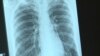

В Екатеринбурге официально объявлено об эпидемии ВИЧ. Свердловская область находится на первом месте в России по числу заболевших на сто тысяч населения. Инфицирован каждый пятидесятый житель Екатеринбурга. Часть заболевших находится в том числе и в колониях Свердловской области – там болен каждый пятый, 5 тысяч человек из 25 тысяч. Нужное лечение получают меньше половины из них, информирует Радио Свобода.

По официальной статистике, предоставленной пресс-службой ГУФСИН Свердловской области, только за январь и февраль 2019 года в лечебно-исправительных учреждениях умерли от всех причин 25 человек, из них по болезни – 24 человека. В том числе, от ВИЧ-инфекции умерло за два месяца 12 человек, то есть половина.

Основным источником информации для заключенного обычно становятся не врачи, а сокамерники, которые склонны недооценивать опасность заболевания и преувеличивать побочные эффекты от терапии. По статистике за 2018 год, всего 48% ВИЧ-инфицированных людей в колониях области получают нужное лечение.

В апреле 2016 года Анне сообщили, что Алексей, который тогда сидел в ИК-2, попал в больницу с высокой температурой, после чего его отправили в ЛИУ-51 (Лечебное исправительное учреждение 51 ФСИН России. – РС), где отбывают наказание и параллельно лечатся заключенные, больные туберкулезом и ВИЧ.

ВИЧ-инфицированных в Екатеринбурге лечат в Свердловском областном центре профилактики и борьбы со СПИД. Но это только поликлиника. Специального стационара для ВИЧ-инфицированных нет. Когда они заболевают, к примеру, пневмонией, их, как правило, отвозят в туберкулезный диспансер. В других больницах ВИЧ-инфицированных пациентов, по их собственным рассказам, принимают очень неохотно.

ЛИУ-51